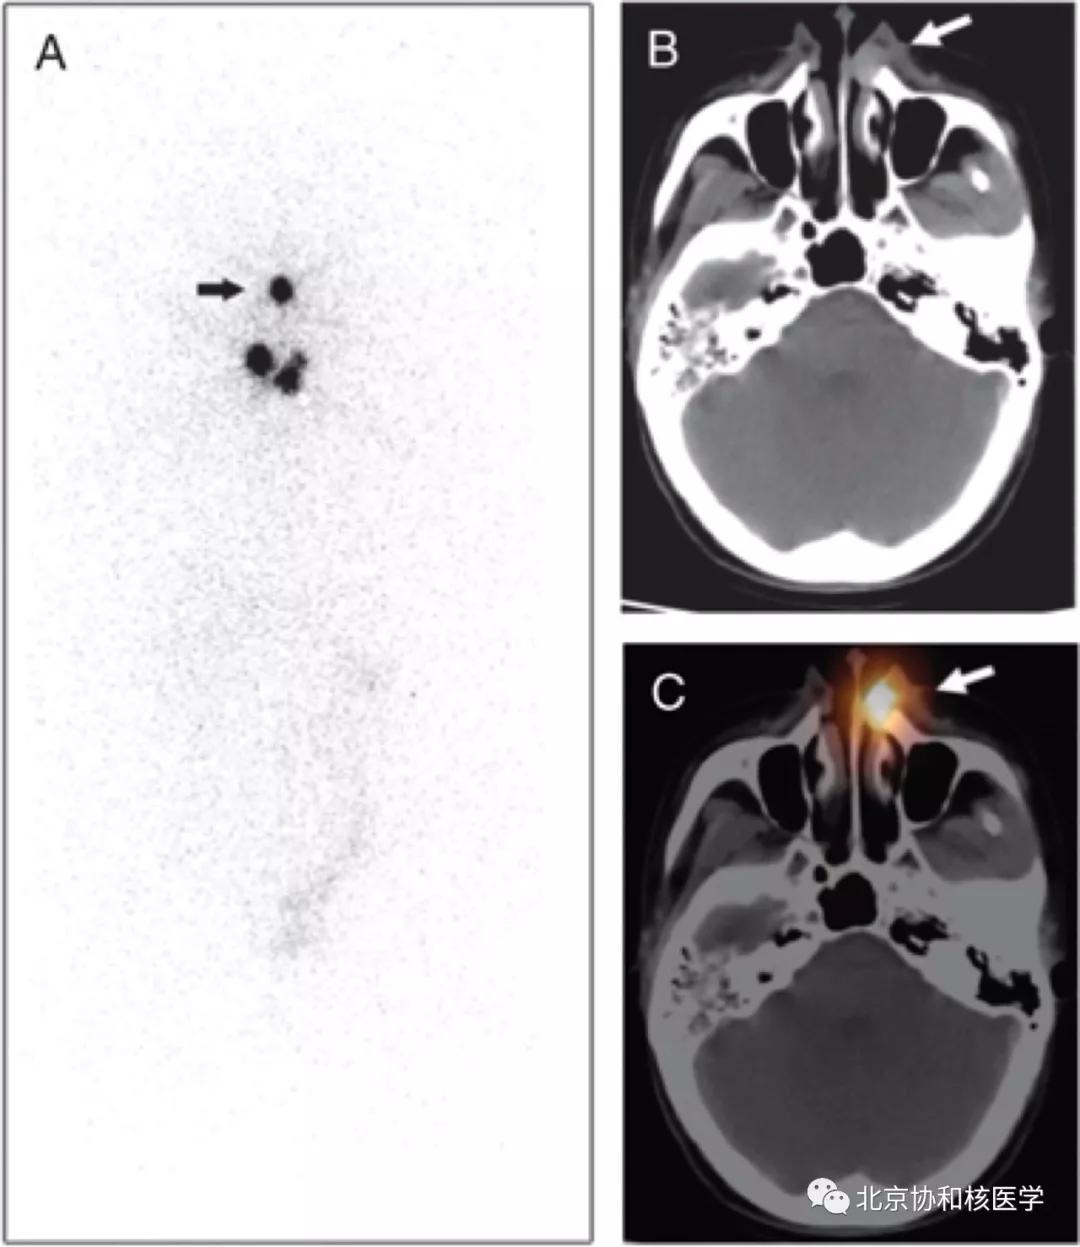

鼻骨骨样骨瘤所致碘摄取,腹部另可见由于巨大肾囊肿所致碘异常摄取: